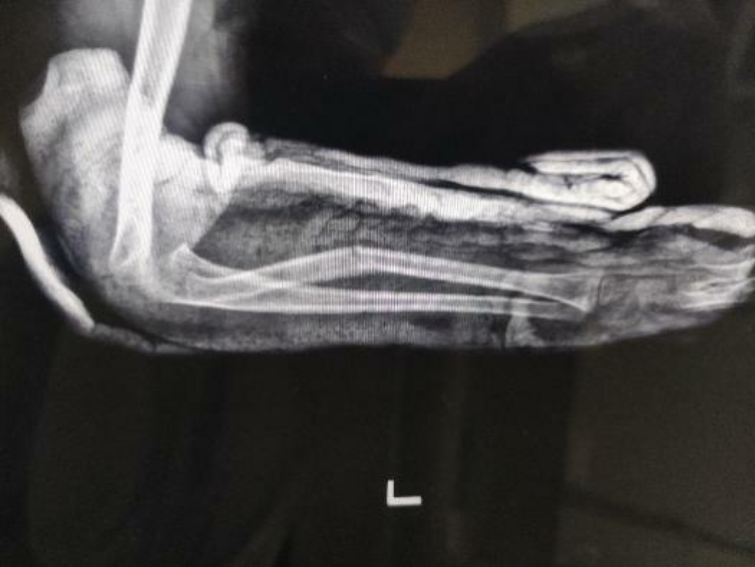

年仅6岁的小照(化名)不慎摔倒,导致左前臂出现畸形,当地医院x线显示左桡骨中段骨折。父母辗转多院,但经石膏外固定治疗后,效果仍然不佳。复查显示,骨折掌侧成角畸形较前增大,对线不良,医生建议手术治疗。小照父亲不忍孩子遭受手术之苦,来到南方医科大学中西医结合医院,寻求中医正骨保守治疗。

医院骨伤科主任黄刚查阅x光片,认为小照此前接受的石膏外固定不能有效维持骨折位置,但可以采用中医正骨手法牵引复位,加上小夹板外固定治疗,这让小照父母重新看到了希望。

左桡骨中段骨折,骨折端掌侧成角,近端内收畸形